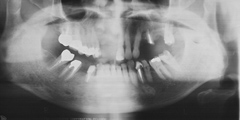

吉本歯科医院においては、口内写真とパノラマレントゲンを撮影し、まずは顎の骨の状態まで詳しく確認しました。

噛み合わせが非常に悪く、上の歯が下の歯にすっぽりと覆いかぶさっておりまともに噛めていない状態であることがわかりました。

(インプラント埋入後のパノラマ写真)